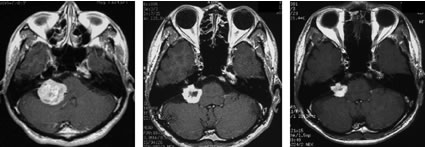

脳動静脈奇形

治療成績は病変の大きさ及び部位によって大きく異なりますが、直径3cm以内のガンマナイフ治療に適した脳動静脈奇形の場合、3年後の完全閉塞率(治癒率)は60−90%前後と報告されています。下図はガンマナイフ治療が奏功し、完全閉塞した典型的な症例です。

左:ガンマナイフ時 中:5年後 右:10年後